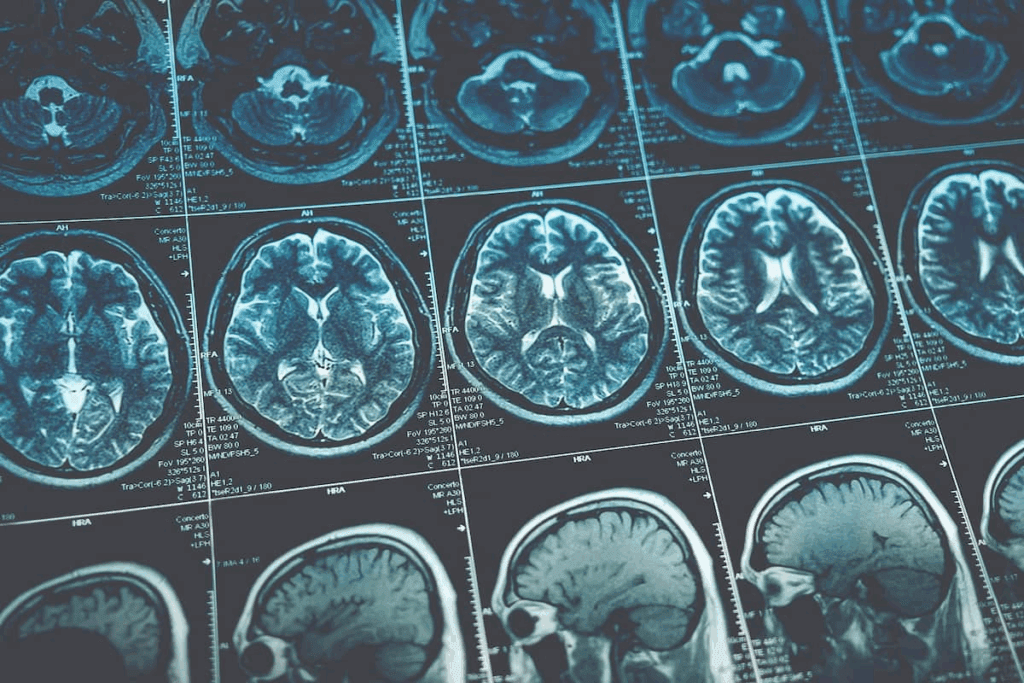

Imaging and Other Diagnostic Tests

To confirm the diagnosis, we use imaging tests like Magnetic Resonance Imaging (MRI) and Computed Tomography (CT) scans. These tests give us clear images of the brain. We can see the tumor, its size, and where it is.

Other tests might be needed too. This includes a biopsy to examine a tumor sample or a lumbar puncture (spinal tap) to check cerebrospinal fluid for tumor cells.